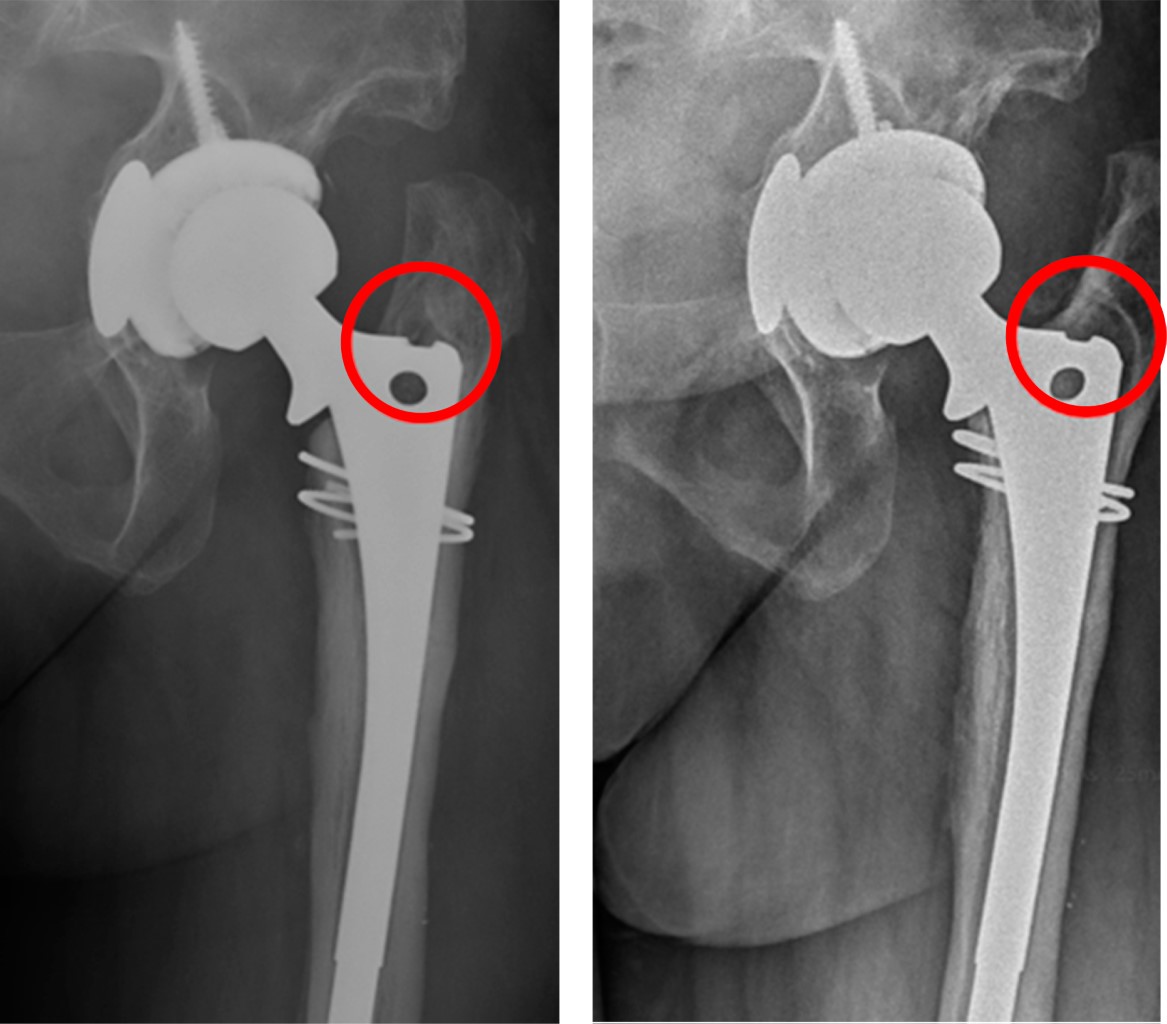

Minimizing risk: evaluation of the relationship between femoral stem loosening and the risk of presenting with peri-prosthetic hip fracture

Introduction: evaluation of predictors of periprosthetic fracture in loosened femoral stems. Material and methods: retrospective case-control study comparing aseptic loosened stems in two groups: cases: patients who experienced periprosthetic femoral fracture before replacement could be performed (n = 9). Controls: experienced prosthetic replacement without fracture (n = 19). Results: pain intensity (VAS) was the most important aspect (p = 0.01), predominating in the controls. The simple radiological parameters did not show statistically significant findings predictive of peri-prosthetic fracture (number of Gruen zones, sum of them in mm, stress shielding, pedestal, polyethylene wear, stem subsidence). The role of complementary tests (CT and scintigraphy) for the definitive diagnosis of loosening was relevant, but not significant. The type of implant showed no differences. Overall implant survival was higher in cases than in controls (p = 0.016). This difference continues when comparing each loosened stem until fracture or replacement (p = 0.024). Conclusion: the main factor protecting against fracture is the replacement of a stem with clinical and radiological diagnosis of loosening. Adequate follow-up of the patient plays a determining role in this, especially when considering the greater intensity of pain in the controls, which used to guide surgeons to perform replacements before the fracture occurred. This is reinforced if we take into account that up to one third of the cases did not have regular check-ups, and therefore did not have the opportunity for replacement prior to the fracture. The role of complementary tests (CT and scintigraphy) is also very important, taking into account the low diagnostic yield obtained from simple X-rays.

Figure 4